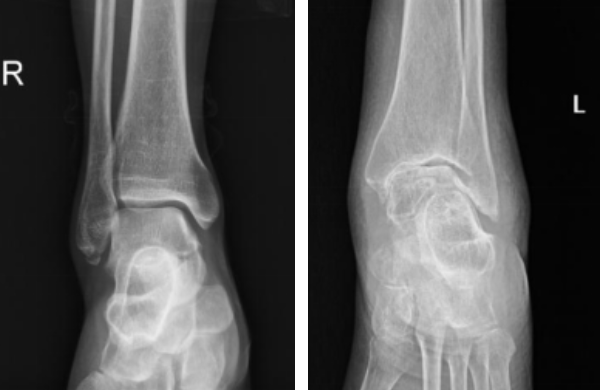

2、足踝部外伤:如足踝部扭伤、足踝部骨折、足踝部的各种韧带、肌腱损伤、外伤后足踝部疼痛,可能会造成患者行走功能障碍。

3、足踝部慢性疼痛:足底疼痛、踝关节骨性关节炎、跖骨头缺血性坏……